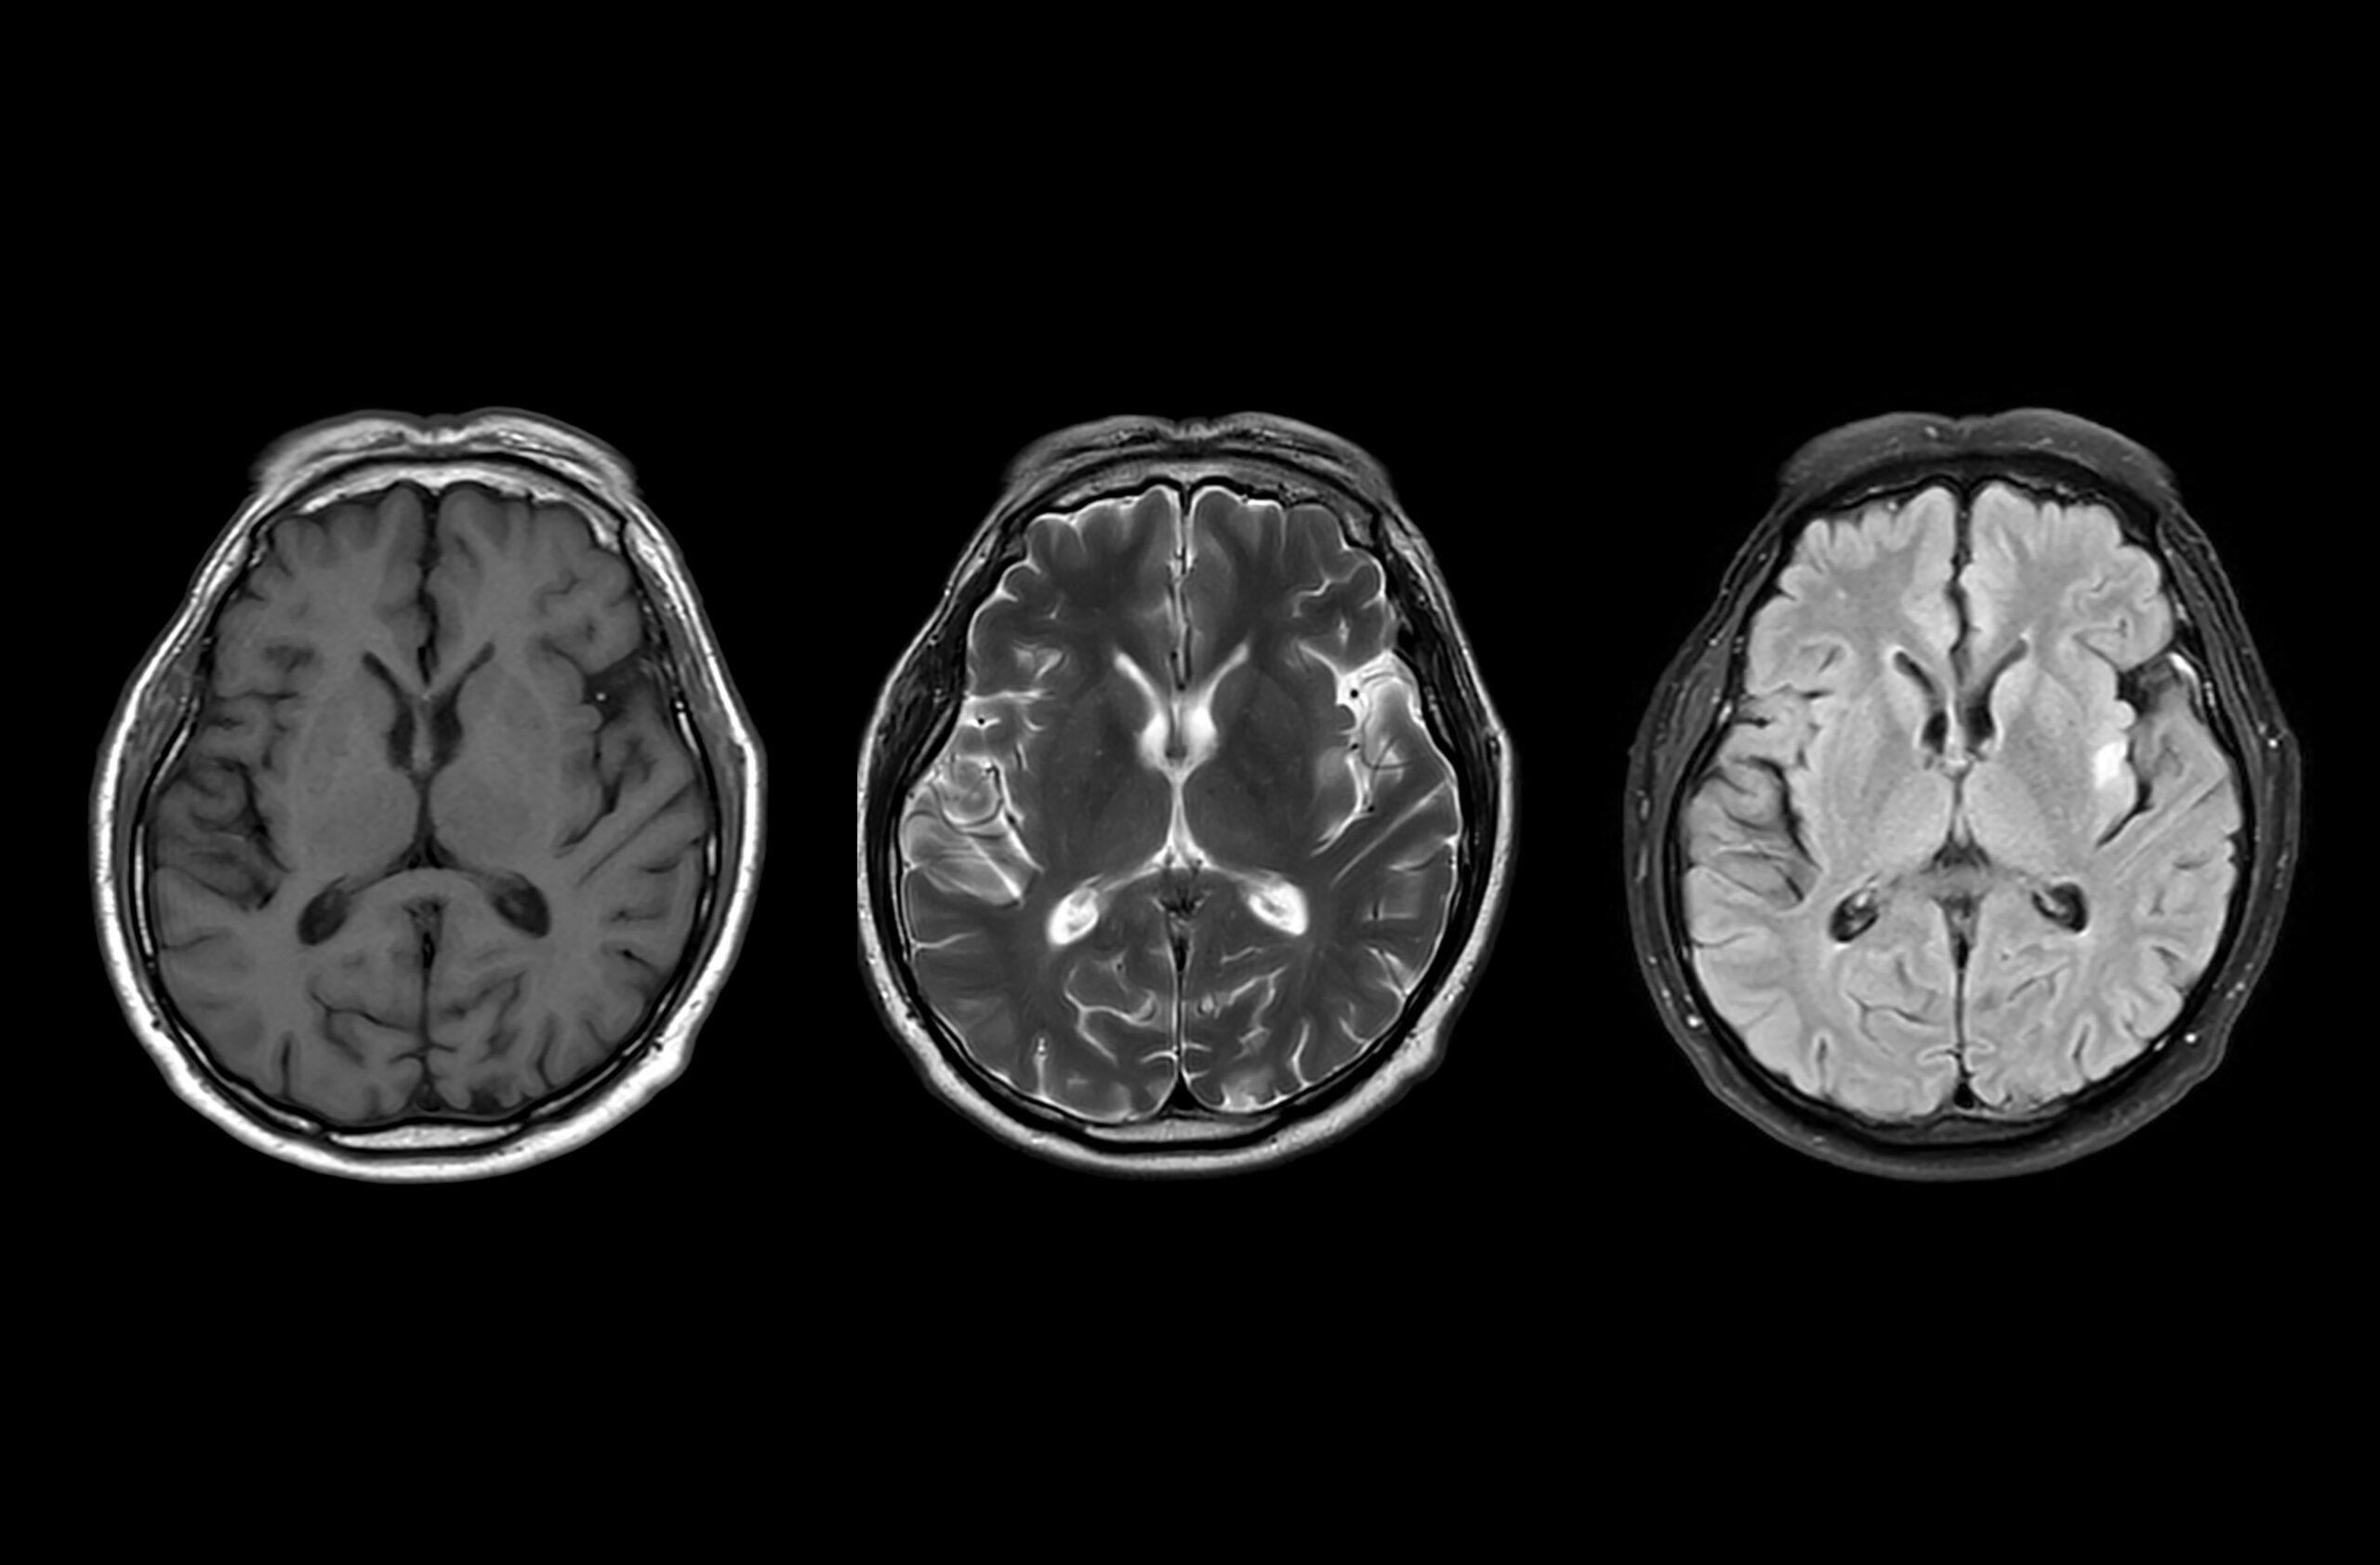

Charles Piller: OK, I’m going to wind us back all the way back to 1906, just briefly, which was the date of the kind of quote, unquote discovery of the disease by [Alois] Alzheimer, a German scientist, namesake of the disease. And he was a pathologist and a clinician, so he was treating a patient who had dementia, and this person ultimately died. And he did an autopsy on her brain, and he saw in the brain copious amounts of amyloid plaques—and this amyloid is a type of protein, and the sticky plaques are the sort of characteristic description of what scientists see as characteristic of this disease—and also another protein that’s called “tau” that tangles within nerve cells. So you have the plaques outside of the nerve cells—and also, it would be later learned that other forms of amyloid protein, soluble forms of the protein, were floating around in the fluid that bathes the brain—and also these tangles.